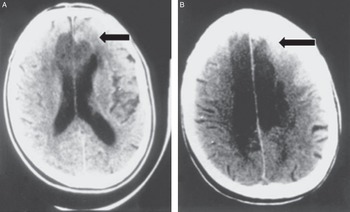

Caplan's Stroke: A Clinical Approach: 9781107087293, Large artery occlusive disease of the anterior circulation,

Large artery occlusive disease of the anterior circulation, 81ctn1kPzML.jpg,

81ctn1kPzML.jpg, Large artery occlusive disease of the anterior circulation,

Large artery occlusive disease of the anterior circulation, Uncommon Causes of Stroke: 9781107147447: Medicine & Health,